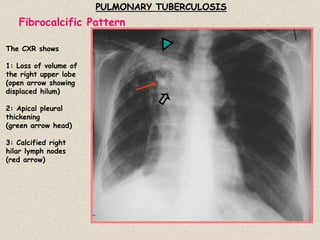

PULMONARY TUBERCULOSIS

The CXR shows

1: Loss of volume of

the right upper lobe

(open arrow showing

displaced hilum)

2: Apical pleural

thickening

(green arrow head)

3: Calcified right

hilar lymph nodes

(red arrow)

Fibrocalcific Pattern